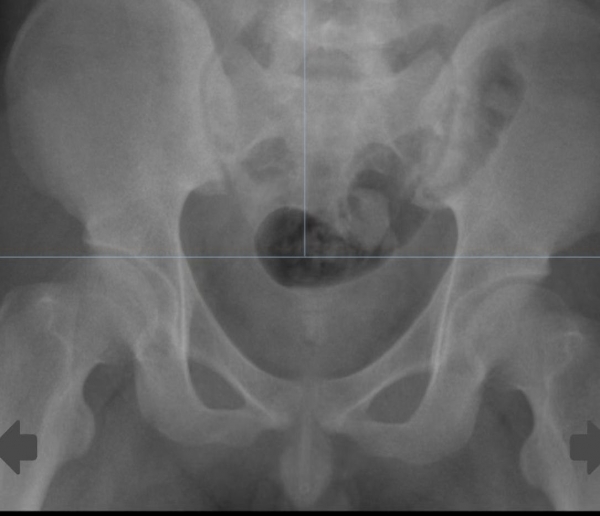

接下来的手术就像在膀胱内"夹娃娃",由于磁力珠质地坚硬、吸附力超强,眼看就要夹出来却又掉了下去,如此反复……最终,向旻主治医师、文豪主治医师凭借精湛的手术技艺和超乎寻常的耐心,采用取石网篮、异物钳等手术器械"轮番上阵",成功将26颗磁力珠"一网打尽",避免了创伤较大的开放手术。术后复查X线显示:异物被完全取尽,小叶也于7月23日康复出院。

术后复查X线显示,膀胱内异物被取尽